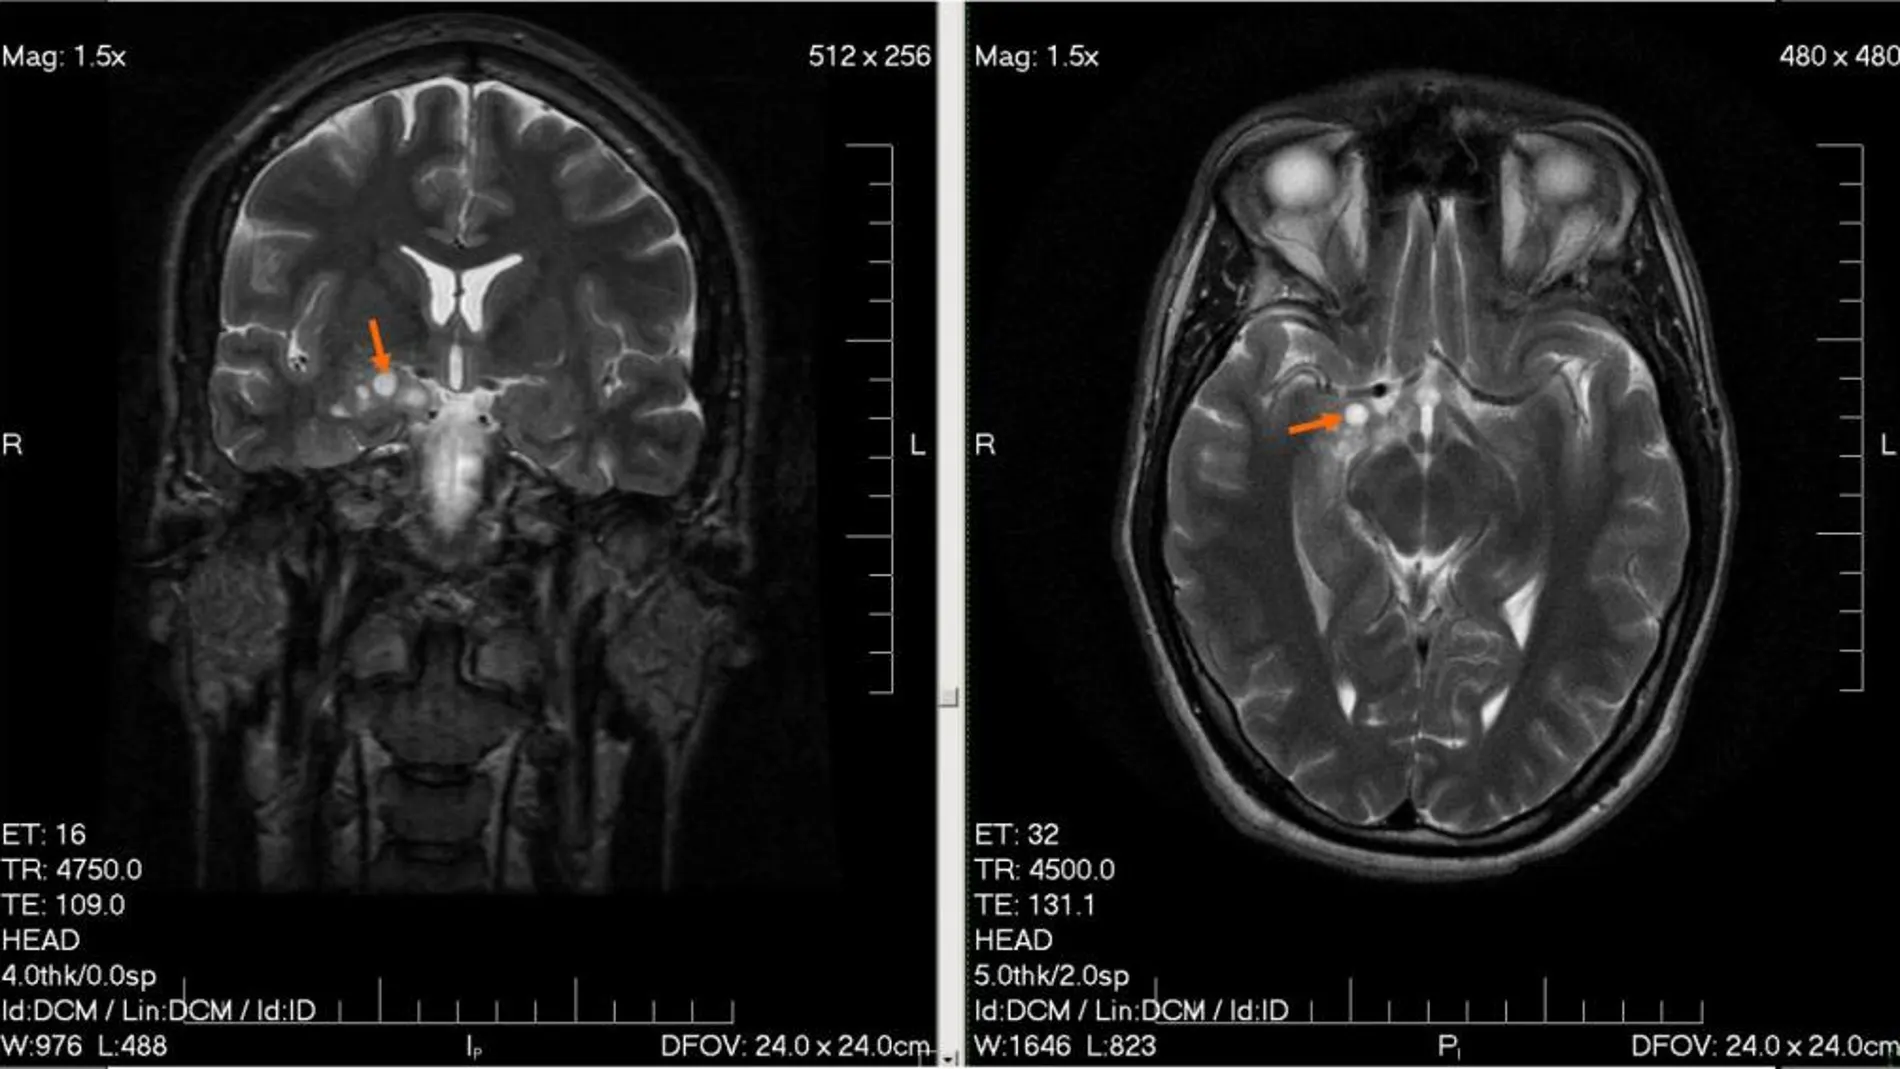

A pesar de todos los esfuerzos realizados por la medicina, los gliomas (tumores del sistema nervioso central) siguen siendo una de las asignaturas pendientes, con pronóstico muy desfavorable y cura imposible, sobre todo para los pacientes más mayores. La esperanza de vida es muy reducida y la cirugía rara vez da resultado.

Ahora, un proyecto financiado con fondos europeos INSERT trabaja en la creación de un sistema innovador que combine las tecnologías SPECT (tomografía computarizada por emisión de fotones individuales) e IMR (imagen por resonancia magnética).

El nuevo sistema permite obtener distintos parámetros que mejorarán la definición de la biología del tumor y aportarán información con la que crear tratamientos personalizados mucho más eficaces, según informa la agencia de la UE Cordis. El sistema se validará a nivel preclínico mediante modelos animales y a nivel clínico en un estudio piloto con pacientes de glioma.